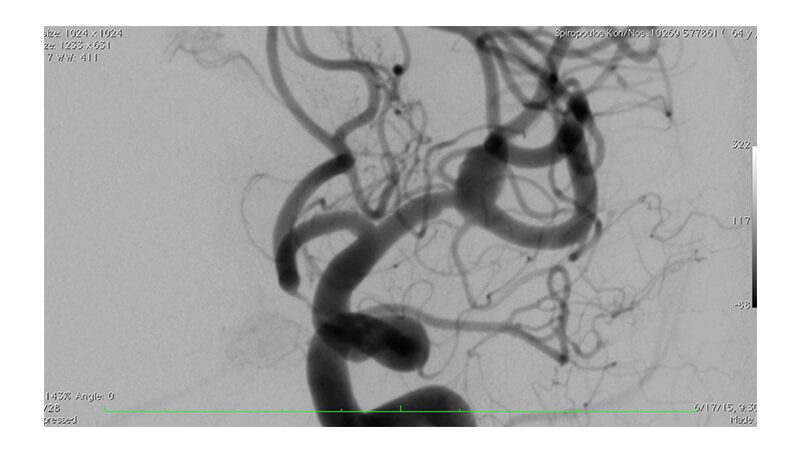

Εικόνα 3, 4: Τοποθέτηση flow diverter stent έμπροσθεν του αυχένα του ανευρύσματος (Pipeline, eV3).

Βλέπουμε την αποκατάσταση της στενώσεως του Μ1 τμήματος.